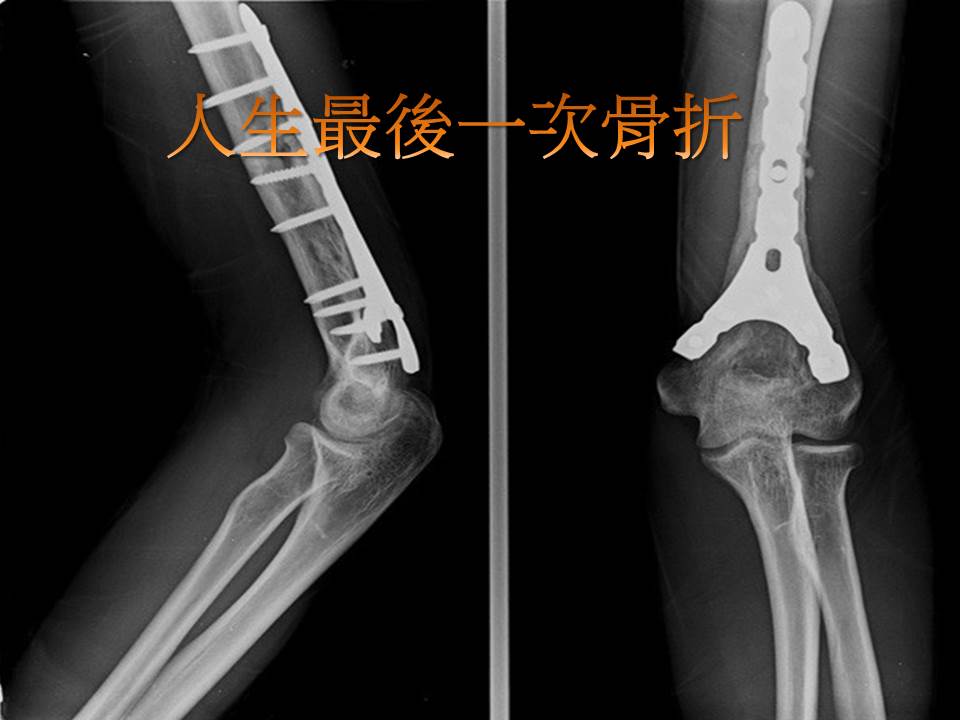

手痛怎么办

健康知识